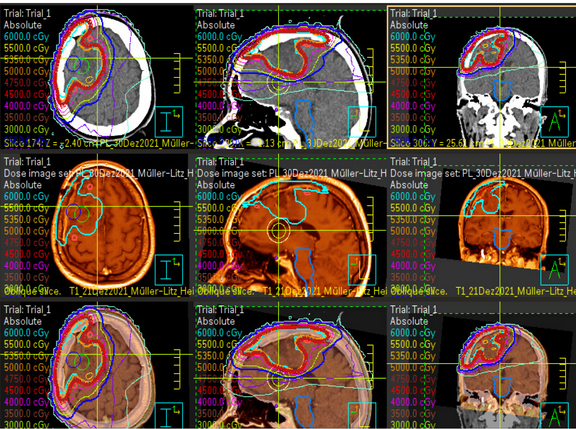

Strahlentherapie

Strahlentherapie ist eine weitere Methode, um Hirntumore zu behandeln. Sie zielt darauf ab, Krebszellen präzise zu zerstören, ohne das umliegende gesunde Gewebe zu beschädigen. Die Klinik für Strahlentherapie führt die Strahlentherapie durch. Unser Team wird Sie dabei mit unterstützen und informieren, um den Prozess so angenehm wie möglich zu gestalten.